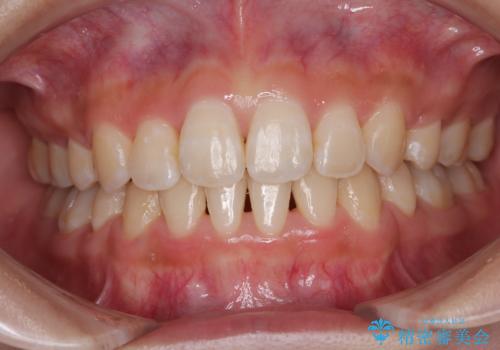

[セラミック治療] 前歯の審美治療に伴う矯正治療